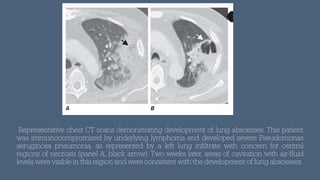

Representative chest CT scans demonstrating development of lung abscesses. This patient

was immunocompromised by underlying lymphoma and developed severe Pseudomonas

aeruginosa pneumonia, as represented by a left lung in

f

iltrate with concern for central

regions of necrosis (panel A, black arrow). Two weeks later, areas of cavitation with air-

luid

levels were visible in this region and were consistent with the development of lung abscesses